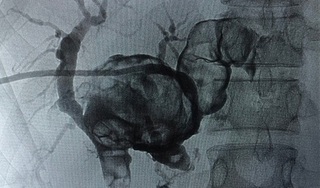

Đau bụng, gầy sút cân, thi thoảng sốt từng cơn kèm rét run không rõ lý do nên người phụ nữ đã đến bệnh viện khám. Kết quả phát hiện sỏi đúc khuôn toàn bộ đường mật trong gan hai bên.